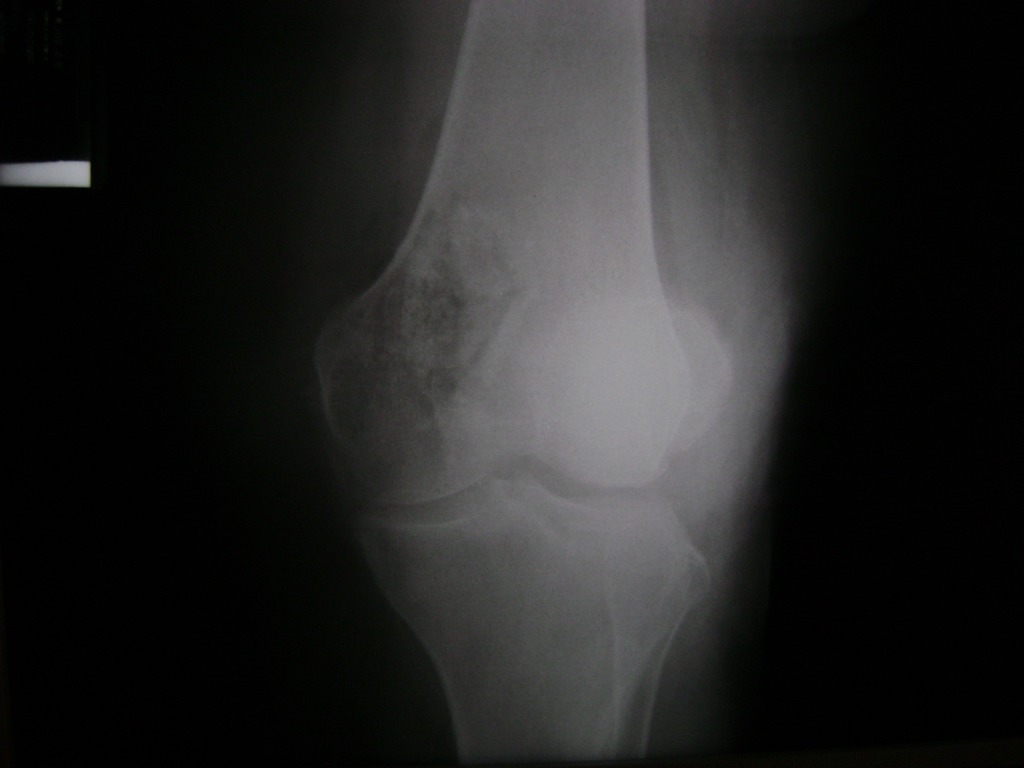

Cirugías de Calcaneo - Rodilla

La artroscopia de rodilla es un cirugía en el cual la estructura interna de la articulación es examinada ya sea para realizar un diagnostico o para realizar un tratamiento, este procedimiento se realiza utilizando un instrumento parecido a un pequeño tubo llamado artroscopio.